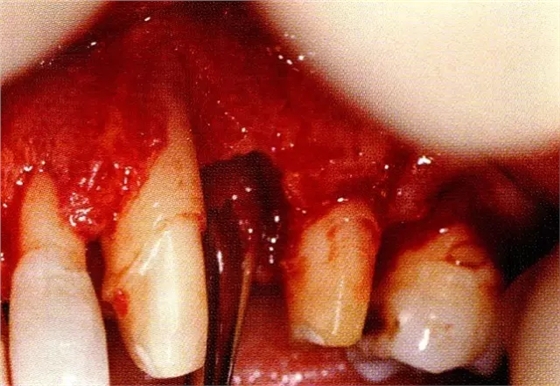

案例3針對3壁性垂直性骨缺損使用非吸收性膜進行再生治療,再翻瓣時進行骨形態(tài)修整的病例。

▲圖7-1左下6近中可觀察到3壁性垂直性骨缺損。此病例考慮到齦瓣供血關(guān)系,在前磨牙部位進行了減張切開,沒有進行縱切開。并利用刮治器、牙周外科用車針進行了徹底的骨缺損部位搔刮。